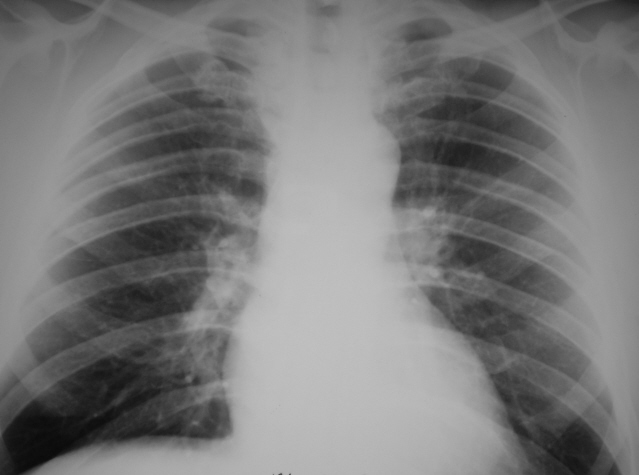

Иллюстрации 1, 2. Рентгенограмма в прямой стандартной проекции и фрагмент её с увеличением. Чисто субъективно, с учетом информации полученной от лечащего врача «придрались» к левому корню, «заметили» тяжистость кверху, хотя такая – же определяется и справа.